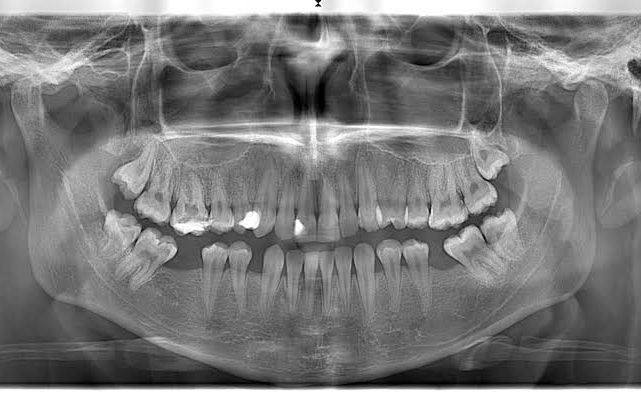

İlerleyen teknoloji ile görüntüleme teknikleri ilerlediği gibi diş görüntüleme seçenekleri de artmıştır. Bu ilerleyen teknoloji ile dişteki sorunları görmek tedaviyi daha kolaylaştıracak, daha iyi sonuçlar alınmasını sağlayacaktır. Film ile diş ve çenedeki patolojik görünüm elde edilir. Röntgen ile alt ve üst çenelerdeki oluşumlar ve en küçük detaylar rahatlıkla görülebilir. Tedavi yolunun belirlenmesi için ilk muayeneden sonra çekilmesi önerilir.

İlk olarak röntgen odasına alınan hastanın çenesi röntgen cihazının baş kısmına yerleştirilir. Baş kısmını iki kısımdan oluşan ince bir aparat çevreler. Tüm düzenlemeler ve ayarlamalar yapıldıktan sonra kafa etrafında dönen cihaz aldığı görüntüleri bilgisayara iletir. Böylelikle görüntüleme işlemi yapılmış olur.